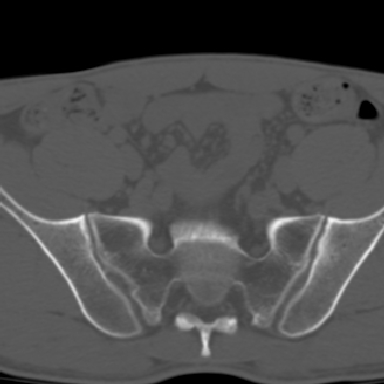

m 30 腰背部不适半年; 清晨时僵硬; 活动症状有所改善

双侧骶髂关节下2/3关节面模糊,毛糙,可见小囊状骨质破坏区.支持强直性脊柱炎.

强直性脊柱炎的早期改变!不仅表现为双侧骶髂关节,第5腰椎与骶椎间的关节突关节也有类似改变。

双侧骶髂关节下2/3关节面模糊,毛糙,髂骨侧可见小囊状骨质破坏区,骶髂关节间隙增宽(软骨破坏期)。支持早期强直性脊柱炎。

双侧骶髂关节下2/3关节面模糊、毛糙,可见小囊状骨质破坏区,呈虫咬状改变,周围可见增生硬化.支持强直性脊柱炎早期表现.

双侧骶髂关节髂骨面硬化,毛糙,小囊变,属于早期强直性脊柱炎